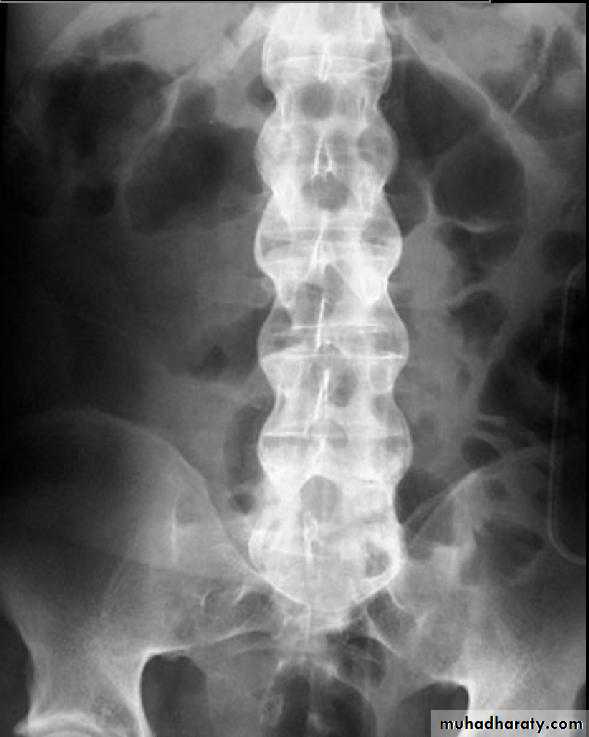

*Bamboo spine (ankylosing spondylitis )

*square shape vertebra (ankylosing spondylits )

Bamboo spine … Ankylosing spondylits

sacroiliitis & facet joint ankylosis

Q..Being charct. Of which one of the following ???*Ankylosing spondylitis

*DISH

Ans…. Ankylosing spondylitis ( is the true answer )